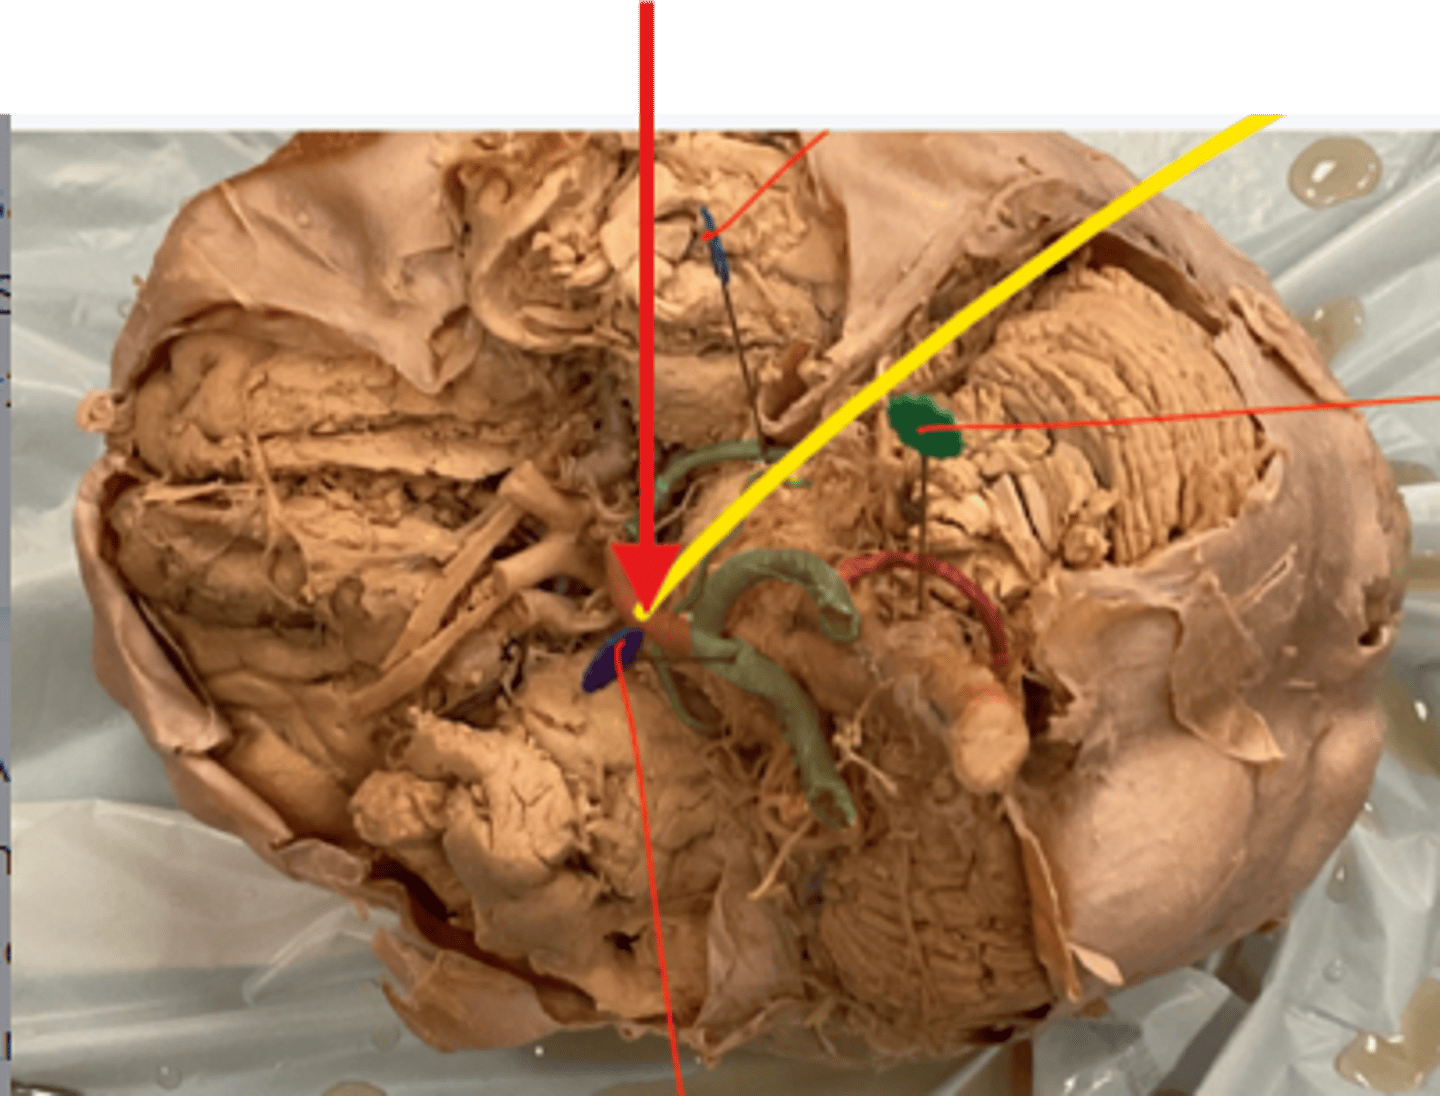

What is the blue arrow pointing at?

What space is the yellow arrow pointing to?

What part is the yellow arrow pointing to?

what space is the yellow arrows pointing to?

what structure is the blue pin in?

What is number 50 or the blue dot?